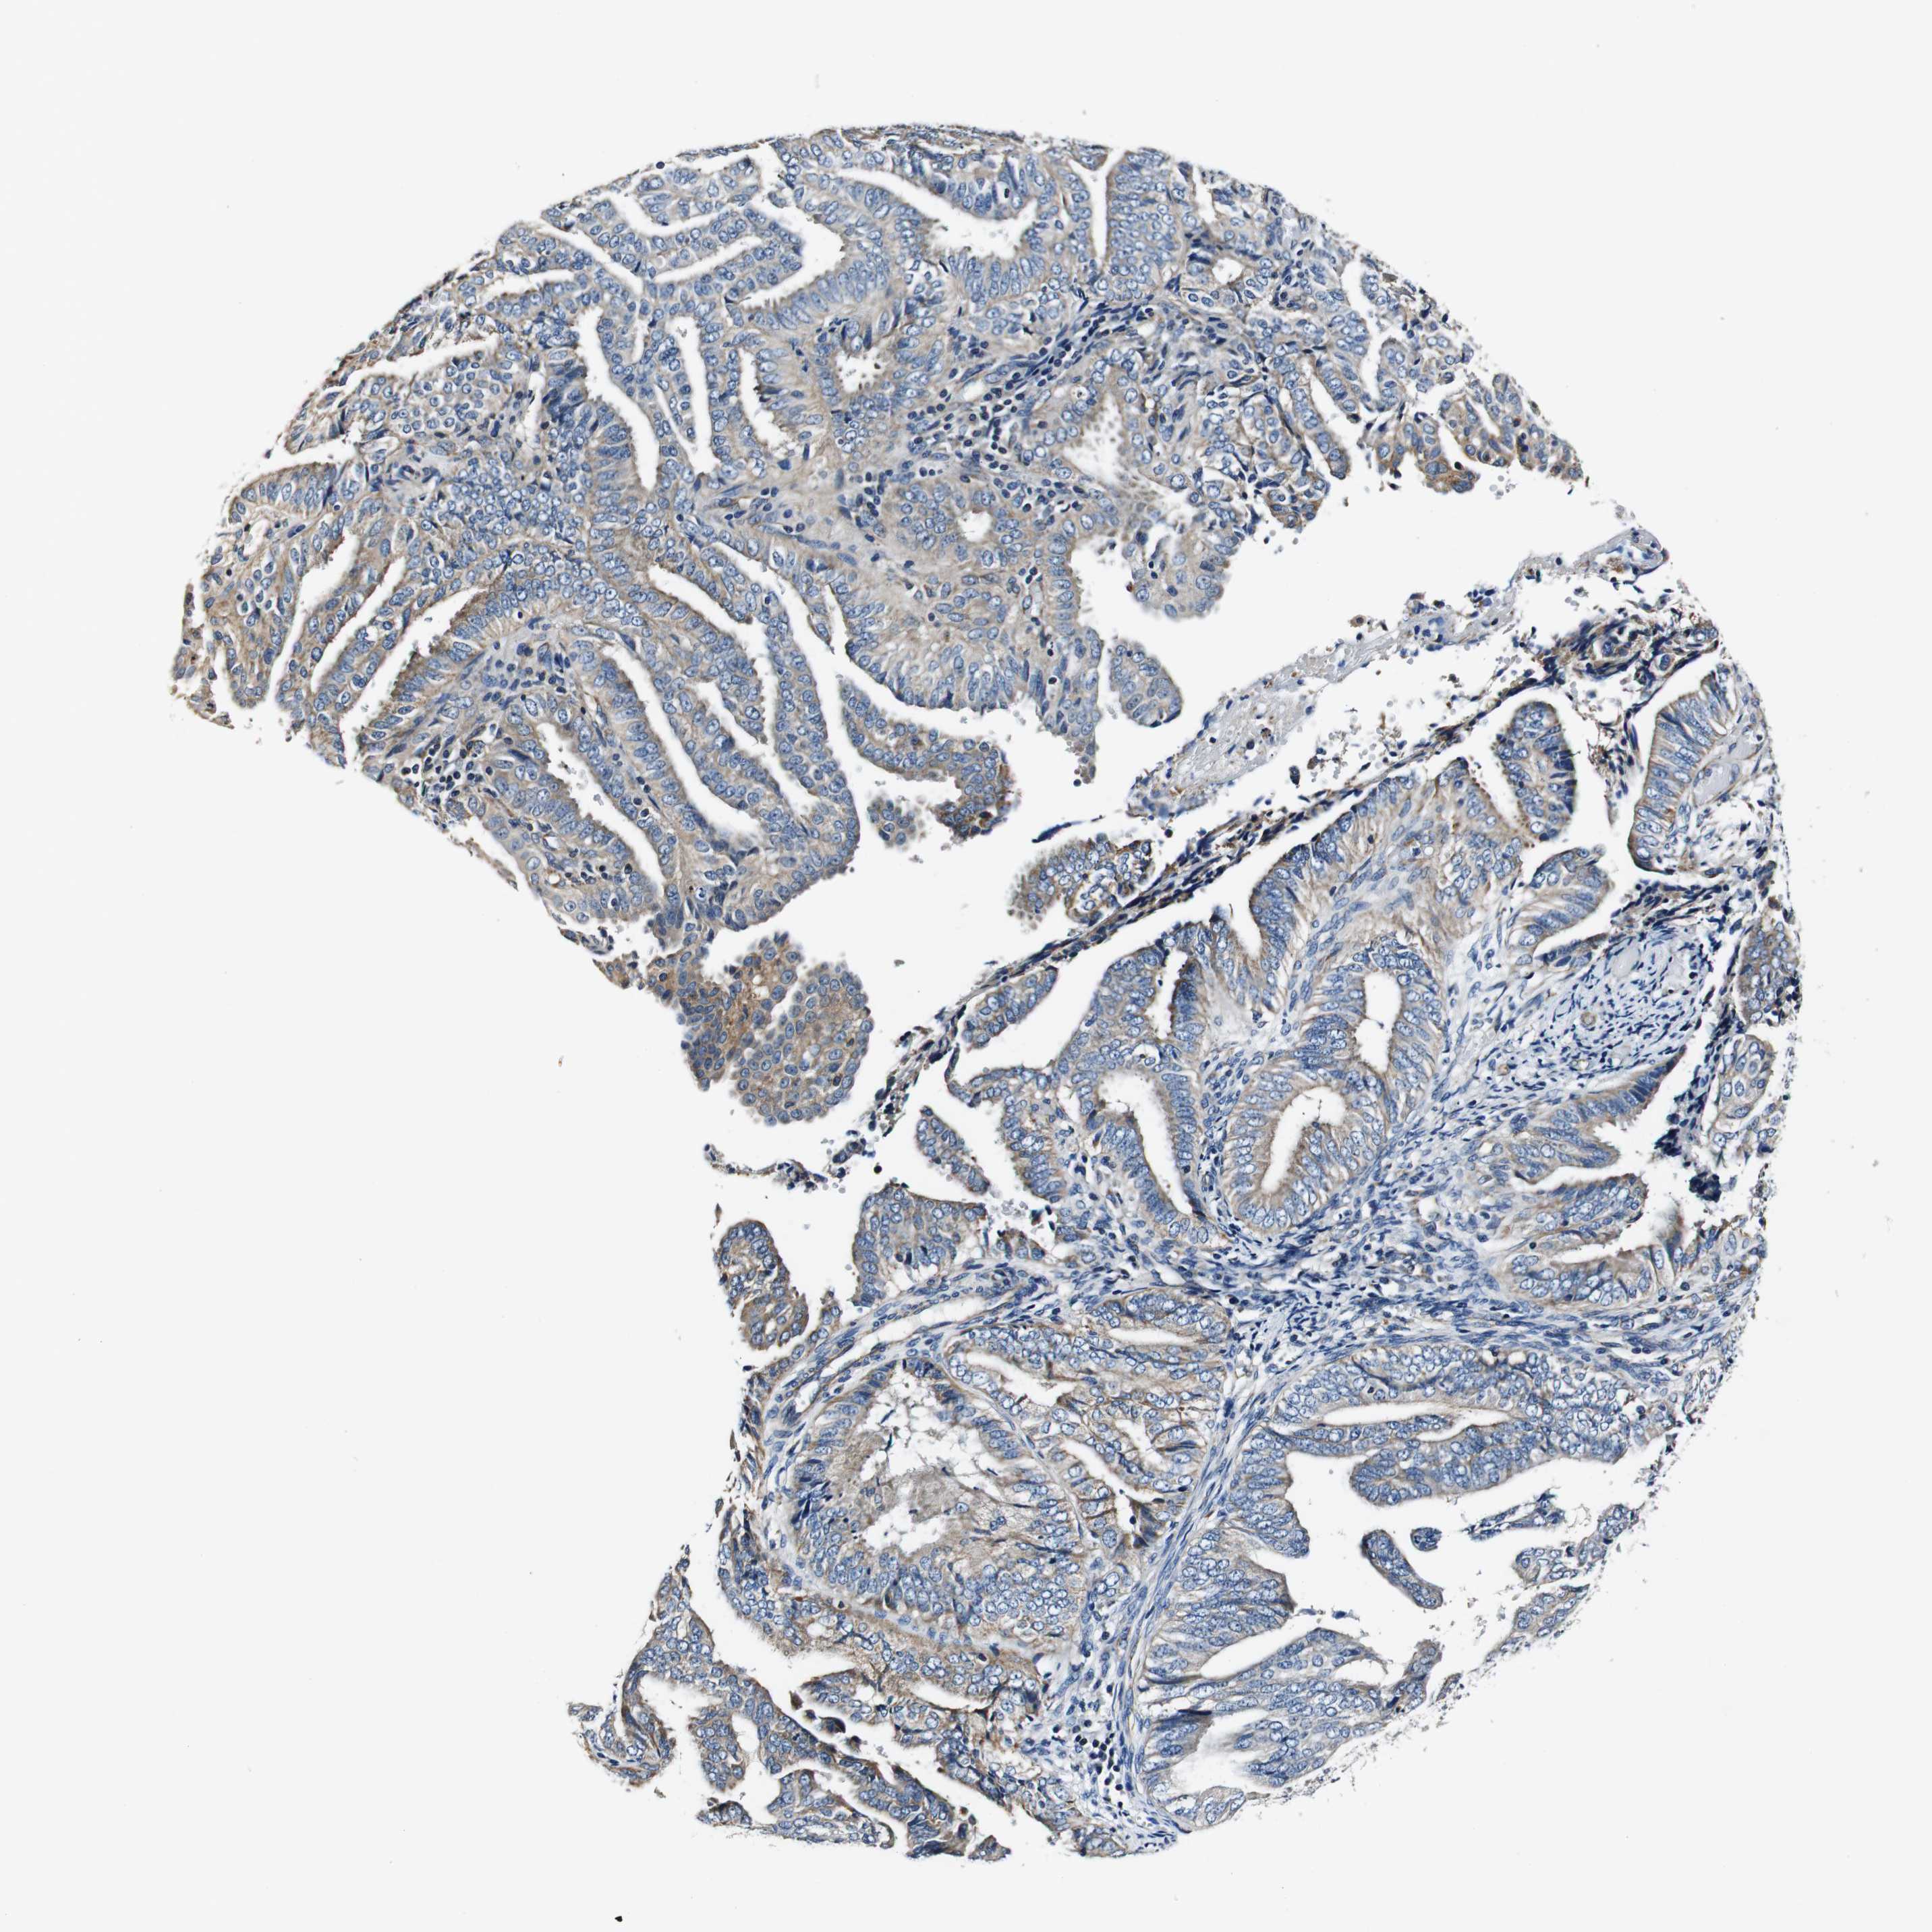

ENDOMETRIAL CANCER - Protein expressioni

A mouse-over function shows sample information and annotation data. Click on an image to view it in a full screen mode. Samples can be filtered based on level of antibody staining by selecting one or several of the following categories: high, medium, low and not detected. The assay and annotation is described here.

Note that samples used for immunohistochemistry by the Human Protein Atlas do not correspond to samples in the TCGA dataset.

Antibody stainingi

Antibody staining in the annotated cell types in the current human tissue is reported as not detected, low, medium, or high, based on conventional immunohistochemistry profiling in selected tissues. This score is based on the combination of the staining intensity and fraction of stained cells.

Each image is clickable and will lead to virtual microscopy that enables deeper exploration of all samples and also displays staining intensity scores, fraction scores and subcellular localization as well as patient and tissue information for each sample.

Antibody HPA007043

Antibody HPA007044

Antibody CAB010052

Staining

High

Medium

Low

Not detected

Intensity

Strong

Moderate

Weak

Negative

Quantity

>75%

75%-25%

<25%

None

Location

Nuclear

Cytoplasmic/membranous

Cytoplasmic/membranous,nuclear

Adenocarcinoma, NOS